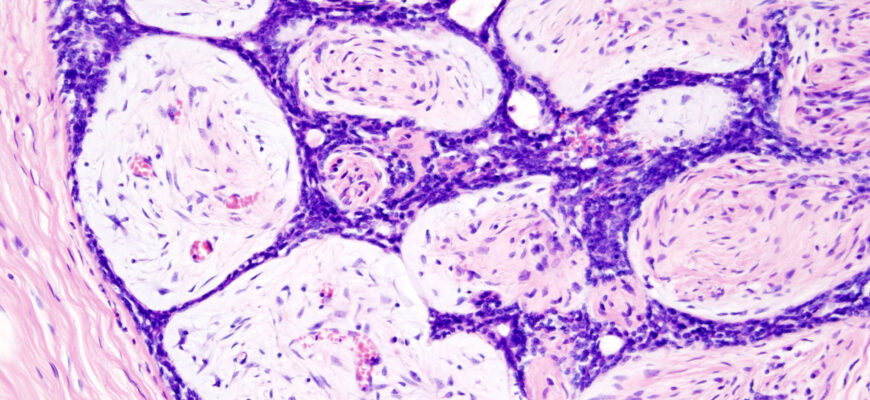

Фіброаденома — ну, це така пухлина. Але не переживайте, вона доброякісна. Зазвичай утворюється в грудях. Часто з’являється в молодих жінок. Страшить своїм виглядом багатьох. Але це не рак. Радше бентежна сусідка, ніж зло з кутка.